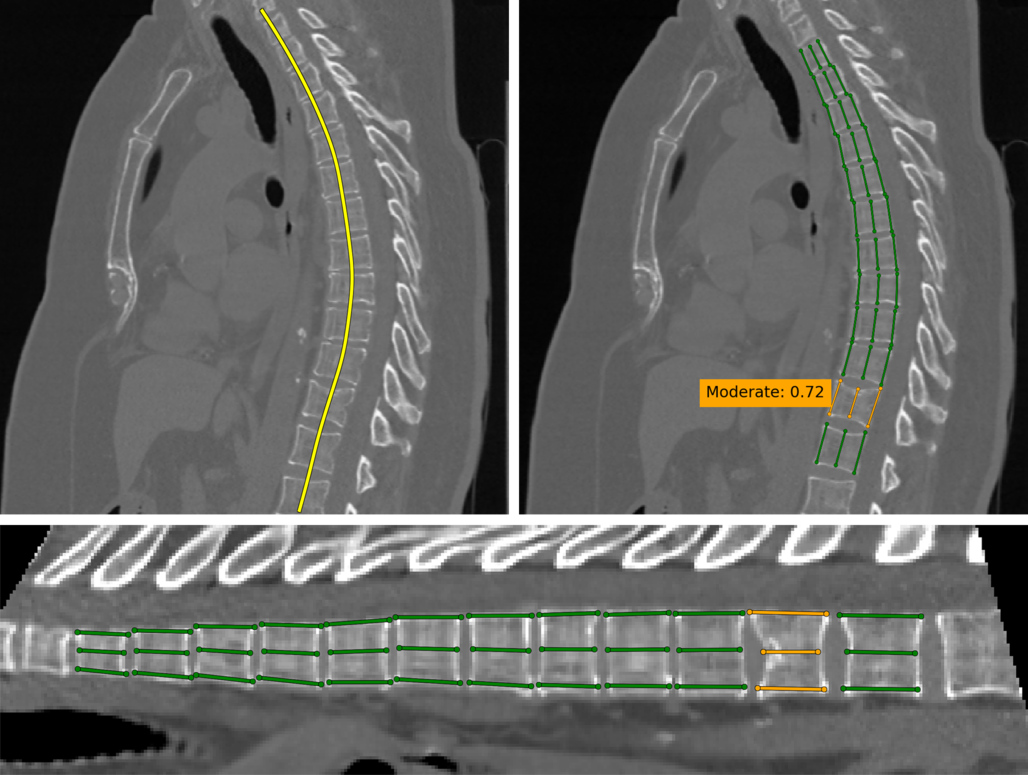

Refer to caption

Figure 5: Two hard examples from the dataset. Colors denote the fractures severity.